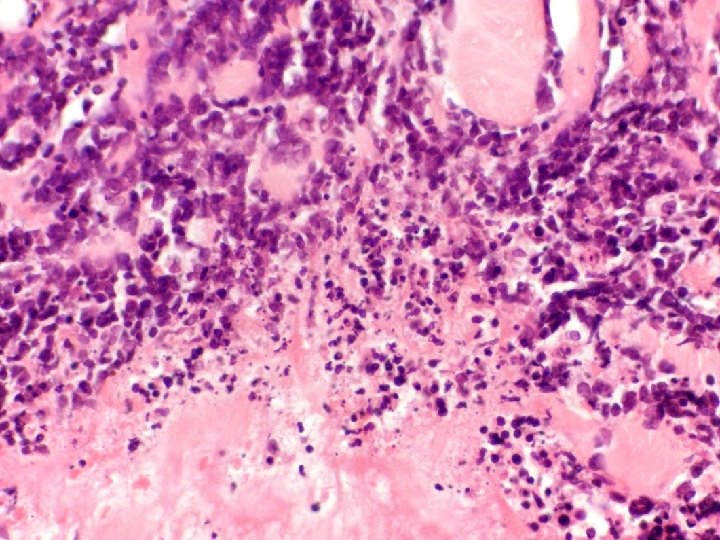

�Case number: 185 �Clinical: Male aged 70 years. ? BCC �Immuno: Pancytokeratin shows strong

�Case number: 185 �Clinical: Male aged 70 years. ? BCC �Immuno: Pancytokeratin shows strong positivity in centre of lymphoid islands. EBV negative.

Most popular diagnosis � Lymphoepithelioma-like carcinoma